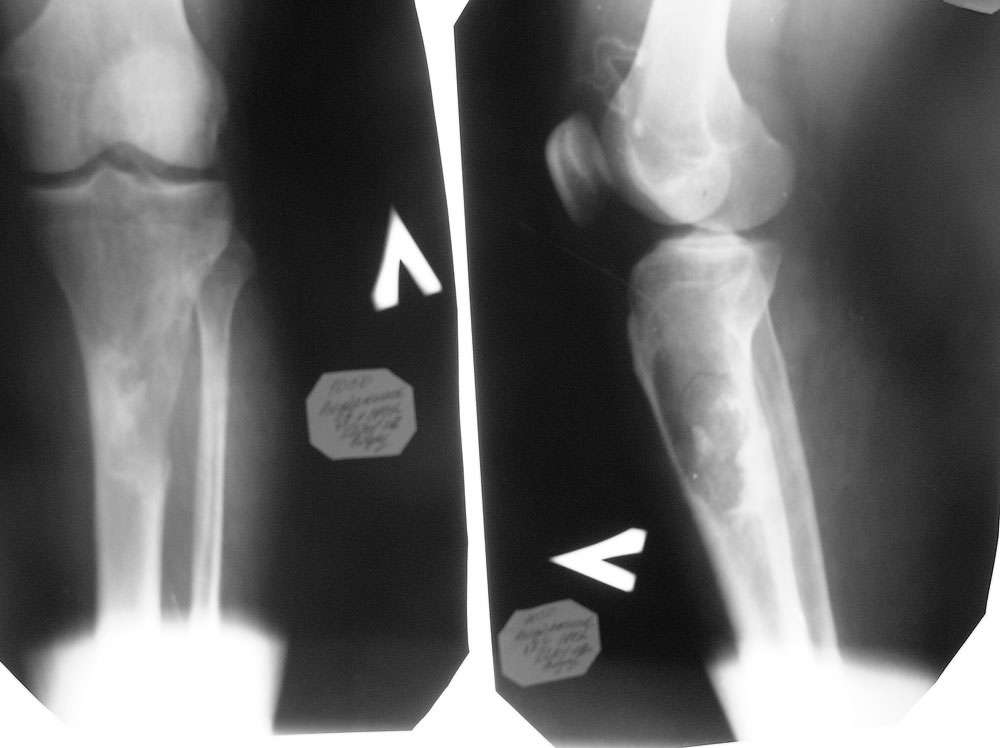

[Ortho] патологический незавершенный перелом верхней трети голени

Пациент 31 года мужского пола, с патологическим незавершенным перелом

верхней трети голени с очагом деструкции бльшого размера поступил к нам

в клинику сегодня. Помогите определиться с тактикой лечения. Сроки

биопсии, делать ли резекцию опухоли одновременно с биопсией и как

замещать дефект. Поделитесь размышлениями, пожалуйста.